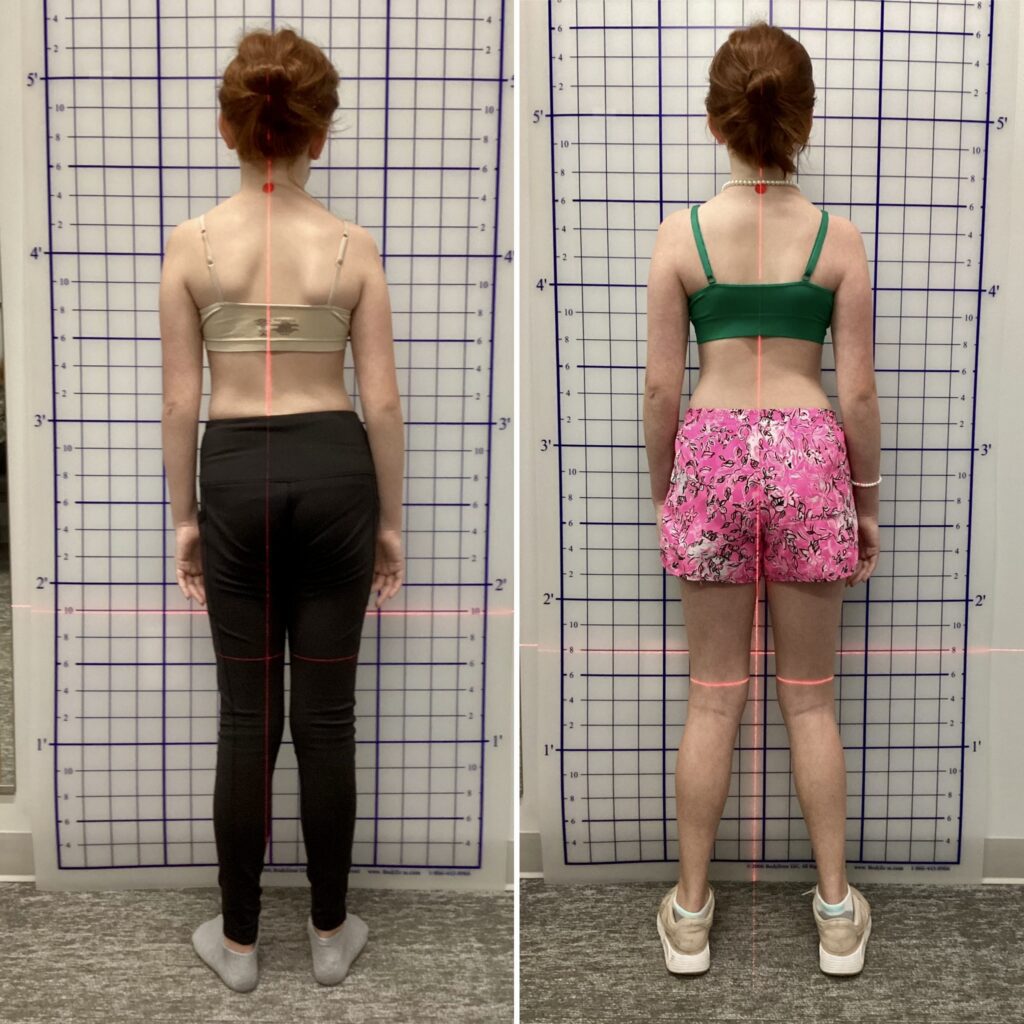

ميل واضح في الكتفين أو الحوض أثناء الوقوف.

اختلاف بسيط في طول الساقين.

ظهور هذه العلامات لا يعني وجود اعوجاج مؤكد، لكنه إنذار مبكر يستدعي فحصًا لدى أخصائي العلاج الطبيعي أو طبيب العظام.

زيارة أخصائي العلاج الطبيعي تساعد على اكتشاف أي ميل في الحوض أو اختلاف في طول الساقين مبكرًا.

فعند تصحيح وضع الحوض ومفصل الفخذ وتدريب العضلات المسؤولة عن التوازن، يبدأ العمود الفقري في العودة التدريجية إلى وضعه الطبيعي، خاصة في المراحل المبكرة.